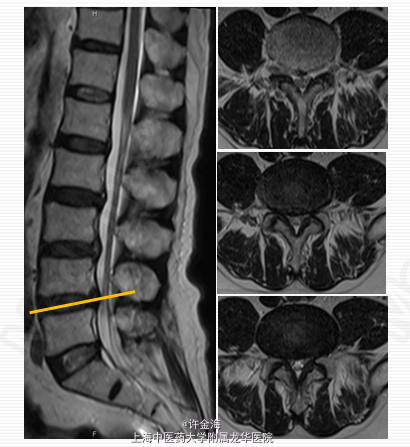

2周后评分:腰VAS2分;腿VAS2分;JOA22分 出院后续治疗:服用中药3月;电针、艾灸每周1次 5月后随访: 复查MRI:游离椎间盘消失 评分:腰VAS0分;腿VAS1分;JOA26分 体检:腰部活动正常,双下肢直腿抬高试验>70°,肌力V级,浅感觉正常,膝踝反射(++),病理征(-)。